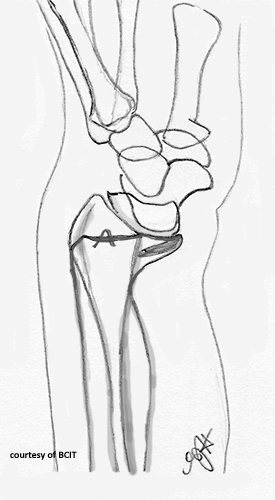

What is a Galeazzi fracture?

Fracture of the distal/mid-radius with dislocation of the distal radioulnar joint.

What is a Monteggia fracture?

Ulnar shaft fracture with anterior dislocation of the radial head.

What causes Galeazzi and Monteggia fractures?

FOOSH with pronation; usually from blunt trauma or falls.

What serious complication can occur with Galeazzi or Monteggia fractures?

Compartment syndrome — increased pressure within a muscle compartment, potentially leading to tissue damage.